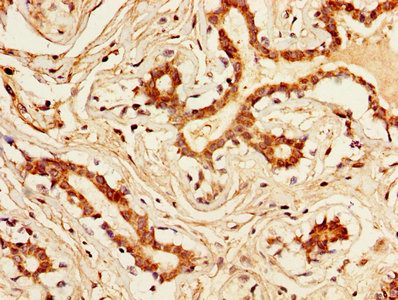

KLK1 Antibody (CSB-PA012446LA01HU)

驗證數據

IHC image of CSB-PA012446LA01HU diluted at 1:300 and staining in paraffin-embedded human breast cancer performed on a Leica BondTM system. After dewaxing and hydration, antigen retrieval was mediated by high pressure in a citrate buffer (pH 6.0). Section was blocked with 10% normal goat serum 30min at RT. Then primary antibody (1% BSA) was incubated at 4°C overnight. The primary is detected by a biotinylated secondary antibody and visualized using an HRP conjugated SP system.